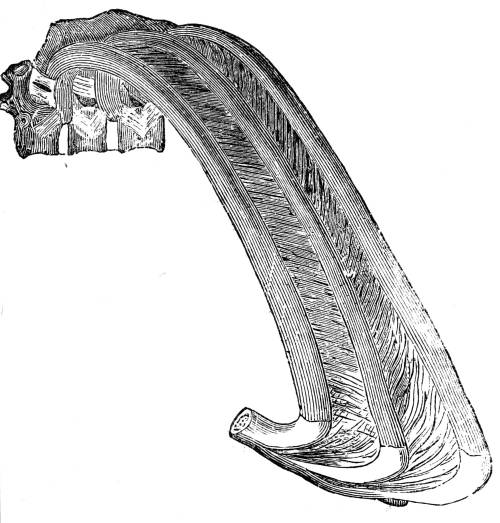

View of the intercostal muscles which fill up the interspaces

between the ribs. These muscles consist of a double

layer of fibres, the external and the internal, which cross

or intersect each other.

382. One part of the action of inspiration consists,

then, of this ascent of the ribs. The ascent

of the ribs is effected by the contraction of a

double layer of muscles called the intercostal (fig.

CXLII. ), placed in succession between each rib;

and which communicate this motion in the fol55lowing

mode. The first rib is fixed; the second

rib is moveable, but less moveable than the third,

the third than the fourth, and so on through the

series: consequently the contraction of the intercostal

muscles (figs. CXLII. and CXLVI. 2) must56

elevate the whole series, because the upper ribs

afford fixed points for the action of the muscles;

and so, when all these muscles contract together,

they necessarily pull the more moveable arches

upwards towards the more fixed (figs. CXLI. and

CXLVI. 2).